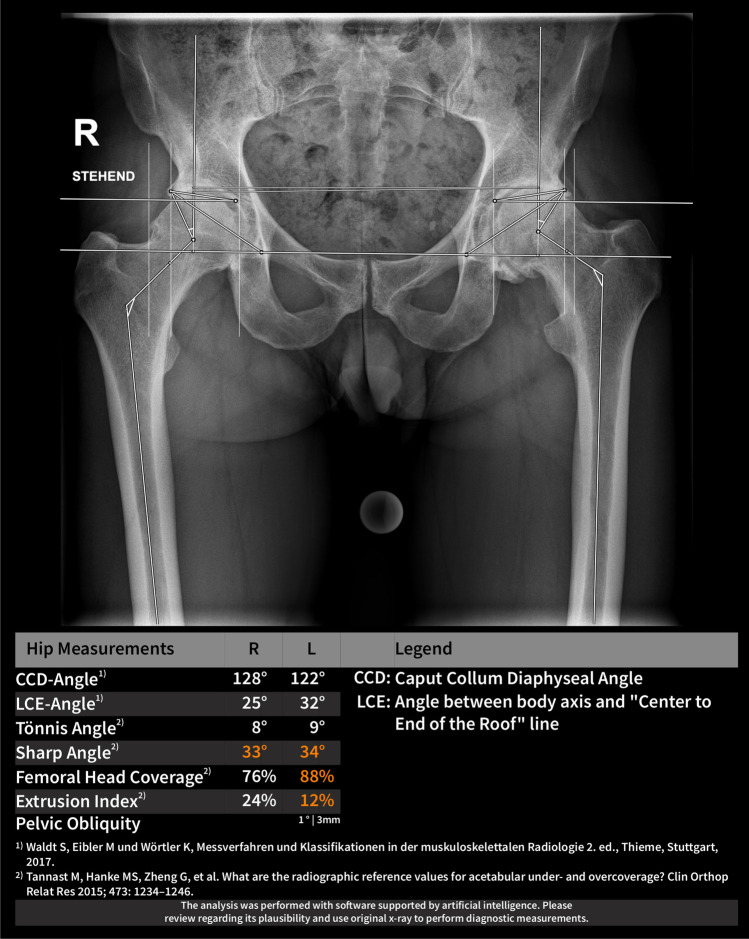

Fig. 2.

Example output of the AI software for the evaluation of pelvic radiographs

The applied AI software HIPPO (Hip Positioning Assistant 1.03, ImageBiopsy Lab, Vienna, Austria) was built to automate angle measurements on pelvic radiographs. The algorithm was trained on over 10,000 radiographs from the OAI (Osteoarthritis Initiative study; US six-site multi-centre), MOST (Multicenter Osteoarthritis Study, US two-site multi-center), CHECK (Cohort Hip and Cohort Knee study; Netherland single center) studies, as well as five sites in Austria (Fig. 1). A multiple U-Net-based convolutional neural network was engineered, trained, optimized, and validated. The data set was randomly split into 80% training, 10% tuning, and 10% internal test sets. The AI software generates a graphical DICOM output with measured values in tabular form and as an overlay (Fig. 2). In case of failed landmark setting outputs are suppressed. The measurements in this study were performed on a laptop running Ubuntu Linux 18.04 LTS with a 4-core Intel i7 (4600U 2.1 GHz) and 12 GB of RAM, with images stored on an external HDD connected with USB 3.0.